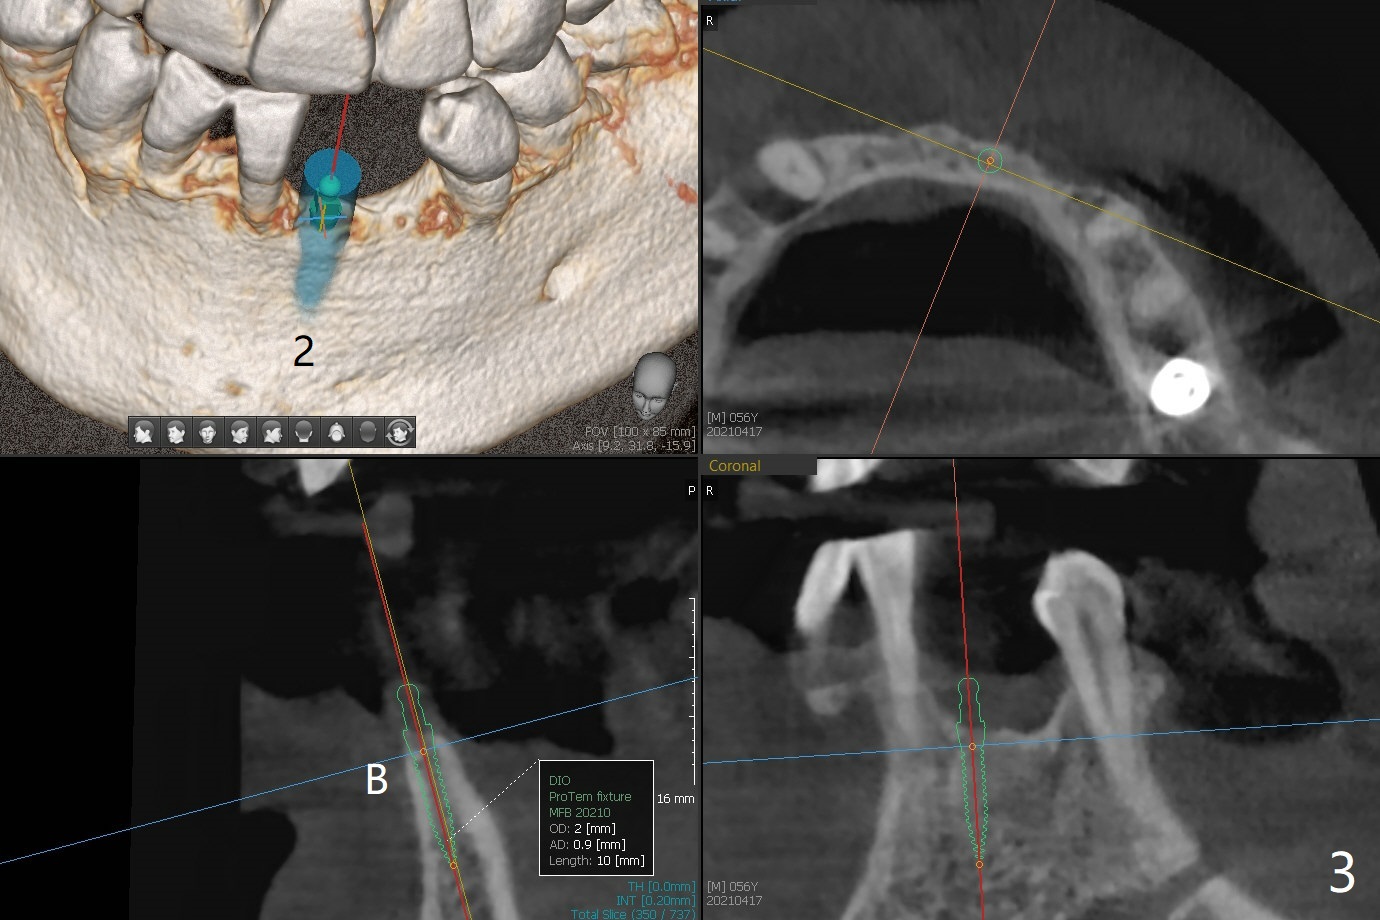

56岁男右下7位点保存一个月,还缺失4个牙齿(图一),左下2,3牙槽嵴特别狭窄,骨皮质为主(图二),应该植入2.0,2.5毫米植体(图三,四),避免复杂植骨术。而右上3骨质也狭窄,但是骨质密度低,几乎松质骨(图五),如果采纳骨膨胀术(高速倒转),植体可以大于4.0毫米,防止植体断裂。左上7骨质宽,但是短,5x8.5毫米植体可能胜任功能(图六)。如果植入10毫米植体,需要做上颌窦提升。